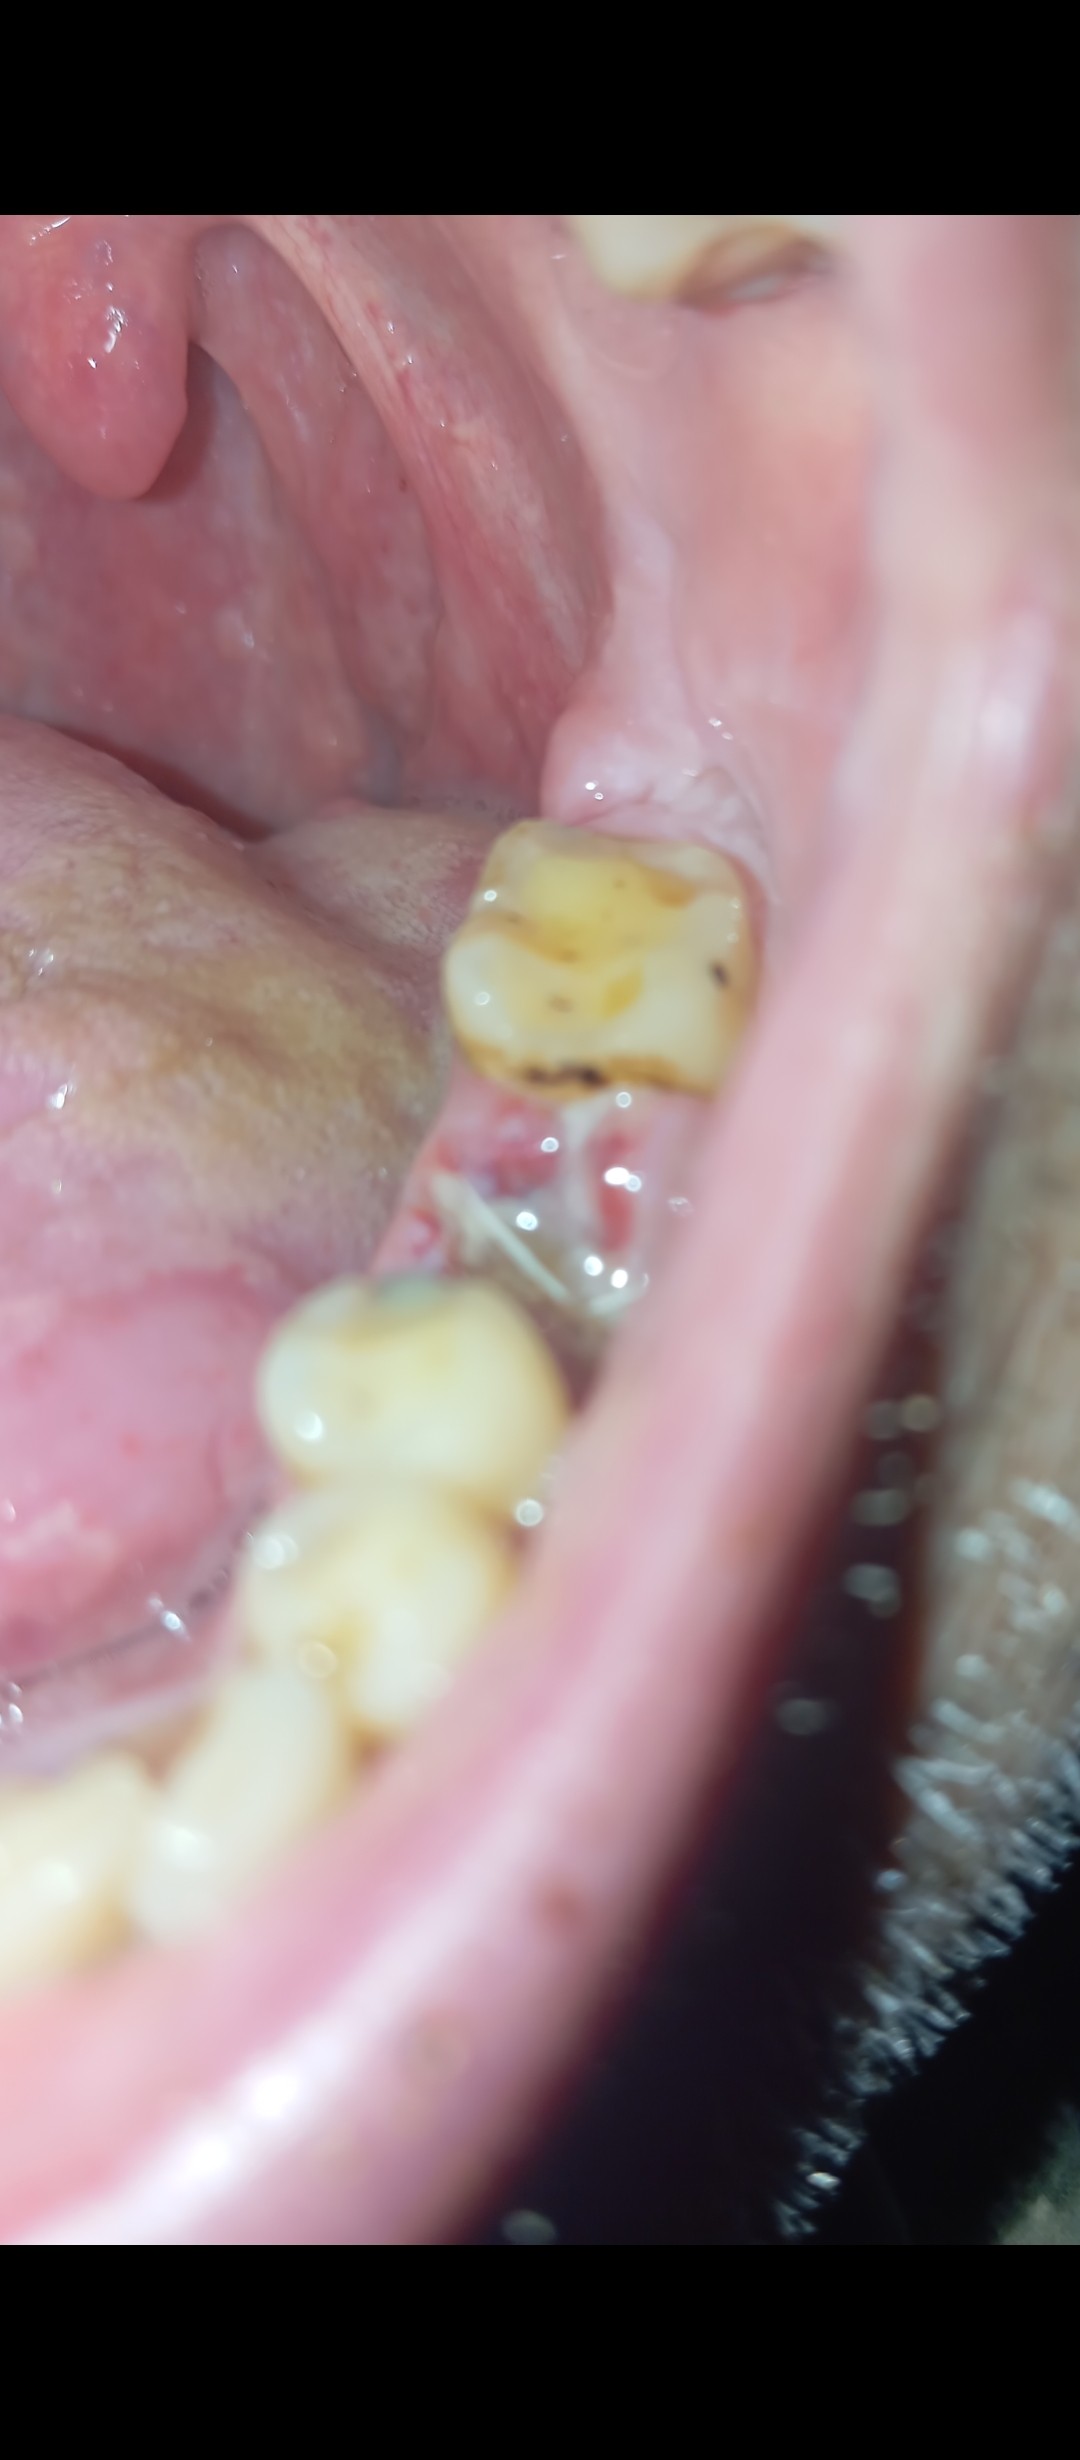

Добрый день. Короче мое самочувствие ухудшилось. Начались сильные боли там где зуб удалили, припухло все. Сегодня поехал к хирургу. Вскрыли. Говорит альвиолит. Начал чистить там ещё и остеомелит.,типа отмерает кость. Почистили, положили лекарство. В понедельник на прием. Выписали Лоратадин, еквалипт. Ибупрофен. Сказали шо антибиотики не надо, потому что я пропил левофлокситин 10 дней уже. Скажите пожалуйста может нужны всё-таки антибиотики? Это ж гной там в кости?

Добрый день. Позавчера был в челестно лицевой областной с сильной болью. Альвиолит. Почистили все. Выписали антибиотик моксиклав и доксициклин. Болит ужасно сильно соседний зуб пятый. Как при пульпите. На нем есть темное пятнышко но свиду зуб нормальный. Я не знаю шо делать уже с ним. Хирург сказал что зуб хороший. Но он же сильно выражено болит. Даже лунка не так болит. Как Вы видите на снимке он норм?

"Десна побелела вся. Эт норм)? " - Это последствия удаления зуба. Это ишемия и некроз слизистой. Ничего страшного. В течении 7 дней она станет красной и где-то через месяц вся лунка затянется новой тканью.

"вот на зубе пятом черная точка может это все же он больной? " - Да, там, скорее всего, имеется кариес под пломбой, но причина ваших болей в данный момент — альвеолит, как осложнения после удаления зуба. А пломбу в 5-ом зубе можно будет заменить после заживления лунки удаленного зуба, т. е. где-то через месяц.

Добрый день Николай Игоревич. Такая беда снова). я перестал пить антибиотики. Потому что уже кишечник от них болит. Вроди все шло на поправку уже. Но вчера вечером опять дискомфорт в лунке. Ночью болело, ныло. Утром продолжается. Десна опухшая и щека немного. До хирурга вообще не знаю когда пойду. Попробую на днях. Почистил ваткой утром вроди гноя нету. Поласкаю календула и стоматофит. Плю хлороксидин. Дырка чета вообще не заростает. Прошло уже три недели от удаления. Ну и 12 дне после чистки альвиолита. Шо опять антибиотики принимать? И чего оно так долго заживает у меня?

"Но вчера вечером опять дискомфорт в лунке. Ночью болело, ныло. Утром продолжается. " — Это нормально. Отлично, что уже нет острых болей в виде прострелов. Красные элементы в лунке — это показатель заживления. Они будут разрастаться и заполнять лунку.